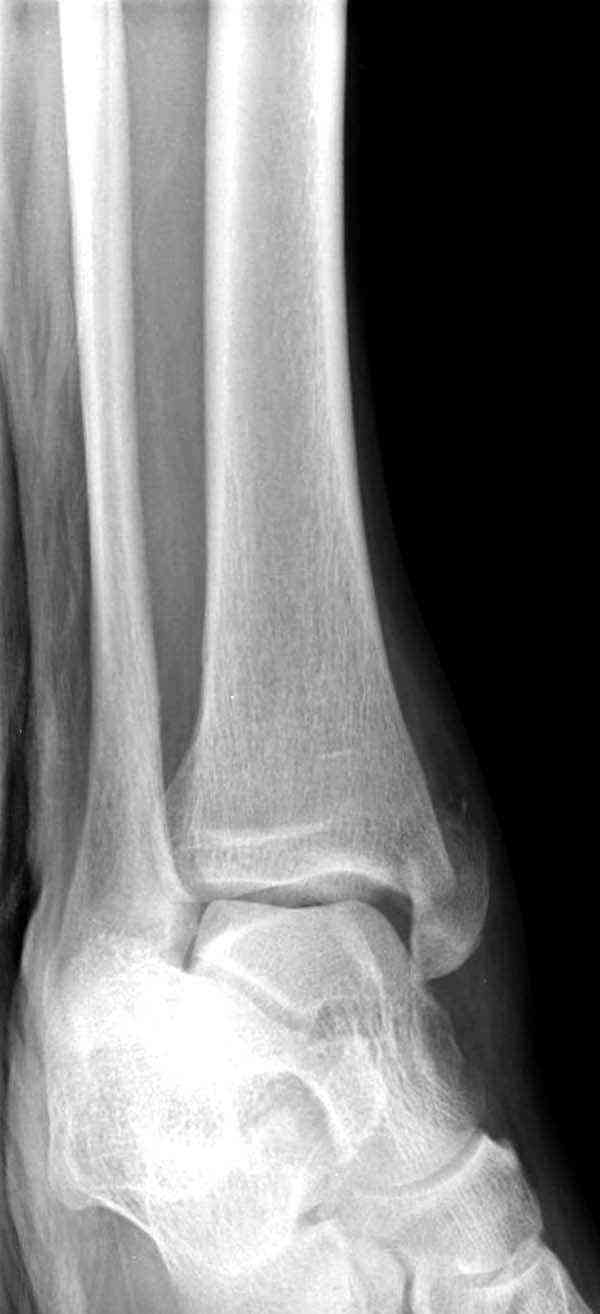

Добрый вечер, коллеги! Хотелось бы увидеть стандартные проекции, прямо, боком и мортиз. Дело скорее всего не в пластине. Стяжка скорее всего не дотянута изначально. Отсюда игра синдесмоза и прорезывание проволоки Вебера. Вообще то стоило бы делать по классике , а именно : Наружная лодыдка - противоскользящая плата по Веберу, над синдесмозом - два позиционных винта ( это "ключи" сустава) внутренняя лодыжка - можно и проволокой, но при адекватной фиксации латерального комплекса.

Визуально никаких вопросов по репозиции не было.Да и на основании чего сомнения,что наружная лодыжка не полностью репонирована или прорезалась проволка ???Я не вижу...Снимок после репозиции справа.

Раз ,есть желание посмотреть другую проекцию выкладываю-ну лучшего качества нет...

Нет первичных снимков, перелом очень низкий и под большим сомнением диагноз разрыва синдесмоза. Медиальная сторона отрепонирована на "хорошо" и, по-видимому, прорезание проволоки произошло во время операции. Без снимков трудно судить о высоте малоберцовой, а лодыжка находится в варусе. Лагирование получилось, но возле тонких шурупов передне-задний шуруп выглядит немного тяжеловато.

Коллеги правы, что при рутинных переломах достаточным бывает обычные снимки с мортизом. А стрессовые рентгенограммы могут уточнить, есть ли разрыв синдесмоза.